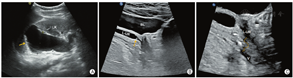

患者女,20岁,因"人工流产术后左下腹痛伴发热2个月余"来我院检查。经阴道超声示:左侧附件区见大小约91 mm×21 mm的无回声包块,其下缘位置较低,达尿道与阴道前壁间隙。初诊超声医生考虑左侧输卵管积脓可能。妇科以"盆腔炎性疾病后遗症:左侧输卵管积脓?"收治入院,完善相关检查后手术。手术前复查超声发现:左肾内可见两组肾窦高回声,上下分布、不相连,其中上组集合系统分离,前后径约41 mm;左侧自上位肾盂发出的输尿管全程扩张,内径约20 mm,下段可见隔膜,隔膜后变细异位开口似与阴道相连(图1)。超声提示:①左侧重复肾,上位肾盂、输尿管积水;②左侧输尿管所见声像,考虑左侧输尿管异位开口于阴道。盆腔磁共振成像(magnetic resonance imaging,MRI)提示:左侧输尿管积水,其末端开口于阴道左前壁,盆腔少量积液。计算机断层扫描尿路造影(computed tomography urography,CTU)提示:左侧重复肾,上位肾盂、肾盏及其连接输尿管明显积水扩张,其末端开口于阴道前壁处,上组集合系统及其连接输尿管未见造影剂填充(图2)。

超声为评估输尿管异位开口于阴道的首要检查方法,其主要表现:①膀胱后方尿道阴道间隙见管状无回声包块,向上始于其引流侧肾脏,向下延续至阴道壁;②彩色多普勒示内部未见血流信号;③常合并有同侧肾发育异常,如重复肾、肾发育不良、肾异位等[4]。此外,还可通过静脉尿路造影(intravenous urography,IVU)、CTU、MRI等检查手段辅助诊断该疾病。部分患者因临床症状较隐匿,易漏误诊,需与以下疾病相鉴别:①输卵管积水,输卵管积水一般走行于卵巢的外侧方,无尿失禁、阴道漏尿等临床症状,而输尿管异位开口于阴道见管状无回声区走行于膀胱后方尿道阴道间隙,输尿管末端开口于阴道壁;②盆腔扩张血管,彩色多普勒可观察到扩张的血管内彩色血流信号。

本例中患者阴道漏尿症状较隐匿,分析病史考虑由于输尿管下段见隔膜且异常开口处较狭窄所致;首诊超声医师未对盆腔包块来源进行追踪而导致误诊。吸取此次超声漏误诊教训,当发现女性患者盆腔管状无回声包块时,应扩大观察范围,判断管状无回声包块的来源、走行、与周围脏器的毗邻关系等;因胚胎时期泌尿系统与生殖系统发育关系密切,当发现无法明确来源的生殖系统异常时,需对泌尿系统进行联合扫查,以期作出准确诊断。此外,对本例患者使用凸阵探头扫查示扩张输尿管末端延伸至阴道前壁,改用线阵探头扫查示扩张输尿管下段可见狭窄,狭窄后输尿管变细异位开口于阴道壁,利用不同频率探头的特点对疾病进行全面观察及诊断,可提供更多诊断信息,减少漏误诊。